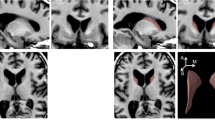

We observed an association between the following clinical variables with GM density, adjusted for age, disease duration, and expanded CAG repeat number (Table 2 and Fig. 2):

UHDRS mood score: The mean score was 10 ± 7.55. Mood score was higher in subjects with higher GM density in region crus II on the right. In region VI on the left, the higher the mood scores, the lower the GM density.

UHDRS-motor score: The mean score was 21 ± 4.24. We found that the higher the GM density in vermis regions VIII and IX, the higher the motor scores. Whereas, the lower the GM density in crus I and II, IV, V, VI, VIIb, and VIII, at right, the greater the motor score.

MOCA score: The mean score was 22 ± 2.12. Subjects with higher cognitive scores had higher GM density in the left region VIII.

Clinical associations and GM alterations. a Negative (blue) and positive (red) correlation between UHDRS-mood score and GM density; b Negative (blue) and positive (red) correlation between UHDRS-motor score and GM density; c Positive (red) correlation between MOCA score and GM density. GM gray matter; UHDRS Unified Huntington disease rating scale; MOCA Montreal cognitive assessment

Although mostly exploratory in nature, the clinical associations revealed some interesting results. UHDRS-mood scores were higher in subjects with lower GM density in region VI on the left, which is directly involved in processing empathy and perception of emotional intonation [22, 23] and higher GM density in region crus II on the right, which is connected to the posterior parietal and prefrontal cortices—limbic areas [24]. There was a positive association between UHDRS-motor score and the GM density in vermis areas VIII and IX, known as the limbic portion of the cerebellum because they are responsible for affective processing, and, with other posterior cerebellar regions, participate in higher cognitive tasks [25]. Structural posterior vermis lesions are the anatomical substrate of the cerebellar cognitive affective syndrome [26]. Since none of those areas are primarily related to motor function, it is possible that they are markers of disease severity, or that there was some collinearity between motor and non-motor scores. Despite understanding atrophy and GM reduction is somehow intuitive, the relationship between increased GM density and mood symptoms is less clear, although this could be due to an adaptive or compensatory mechanism as discussed further below.

Higher motor scores were associated with lower GM density in a large cerebellar region: crus I and II, IV, V, VI, VIII, and VIIb on the right and VI, VIIb, and VIII on the left. These areas are involved in motor control (regions I–V, with a secondary representation in VIIIa/b lobules), multiple domain executive function (lobules VI and VII), saccades refinement, and sequential movements of hands (medially) and feet (laterally) (lobules VI and crus I), which include motor control and motor behavioral action [27, 28]. The ipsilateral somatotopic cerebellar representation justifies the right-sided predominance [27]. Together, those areas are responsible for fine motor control, more complex, and elaborate activities as well as sensorimotor learning.

Patients with higher MOCA scores had higher GM density in lobule VIII on the left, which is involved in sensorimotor tasks and working memory [27], suggesting a cerebellar role in cognitive dysfunction in HD.